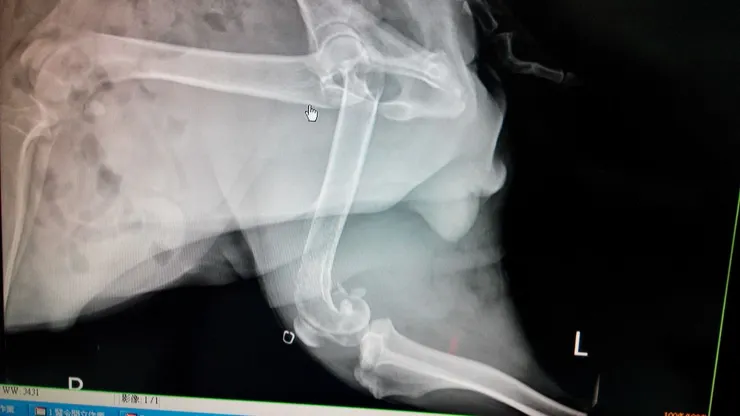

一開始巧克力走路有點一拐一拐的時候,我們並未警覺,獸醫院也想說應該是因為年紀大了,所以關節不好,直到後腿腫了非常大一塊,拍了X片才覺得骨頭部分有些怪怪的。後來到大醫院做細胞切片之後,確診骨癌。